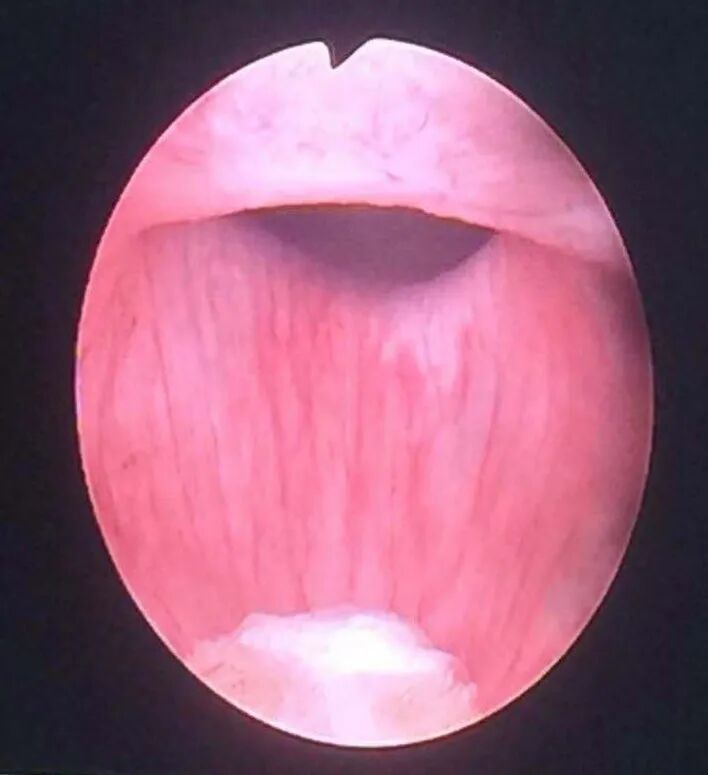

你现在所在的位置:>首页>新闻动态>医院动态>膀胱镜下所见膀胱颈口

图片尺寸708x775